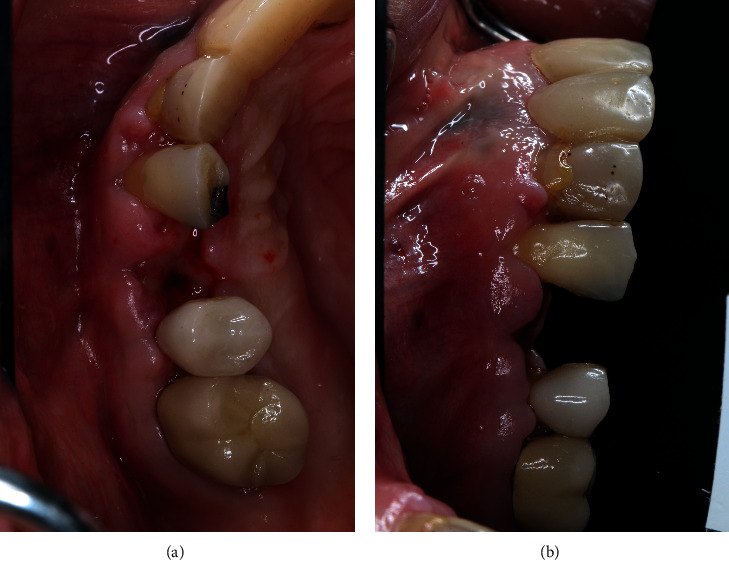

A 64-year-old Caucasian female patient was referred to the Graduate Periodontics Clinic at the University of Florida College of Dentistry for implant placement in the area of #5 (Figure 1). In the patient's self-report about her medical history, she has known allergies to Codeine/Narcotics and some food products, along with hypertension and hypothyroidism. All of her medical conditions were well monitored and controlled by medications. The extraoral and intraoral examinations were performed, including a full periodontal charting examination, periapical radiography, and cone-beam computed tomography. The implant treatment plan was made after assessing the bone volume as well as its proximity to the vital structures in #5 site (Figure 2). After obtaining the patient's consent, the surgical implant placement was performed at #5 area (4.2 mm × 10 mm Astra Tech EV OsseoSpeed, Dentsply International) (Figures 3 and 4). The placed implant achieved good primary stability. The cover screw was tightened, and the site was sutured using a 4-0 chromic gut absorbable suture. The surgery was completed smoothly. The surgical wound showed no bleeding and swelling after suturing. The patient took Ibuprofen for postsurgical pain management. Four days after implant surgery, the patient called the surgeon and complained of the progressing pain, swelling, and burning sensation intraorally and extraorally on her implant surgery side. The patient was scheduled for a follow-up appointment immediately. In the follow-up visit, this patient claimed that from 2nd day after the implant placement, she felt mild to moderate pain at the implant surgery site, which gradually became severe with a score of 8 out of 10 on the pain scale. There was mild swelling with redness on her right side of the face. No significant lymphadenopathy in the orofacial and neck regions was found. The intraoral examination showed erythema of the oral mucosa around the surgical site with purpuric patches on the palate along with few mouth ulcers. The surgical site and adjacent teeth were tender to palpation with hyperplastic gingival (Figure 5). A periapical radiograph was taken during the appointment, and no apparent abnormality was detected (Figure 6). The patient was reassured, and a prescription of amoxicillin (500 mg every 8 hours for seven days by oral administration) was given. The patient texted the surgeon six days later, claiming the symptoms had not been improved since her last visit. Besides, she wrote, “My mother called and reminded me I am allergic to certain metals. For example, I cannot wear some earrings; my ear lobe swells up then bleeds. Do you think this could be the case with this implant?” Based on the patient's history of metal hypersensitivity and her postimplant surgery symptoms, we highly suspected she was allergic to the newly-placed titanium implant on #5. The patient was immediately scheduled for the explant surgery, and the implant on #5 was removed (Figures 7(a) and 7(b)). The extracted site was grafted with freeze-dried bone allograft (Symbios allograft, Dentsply Sirona) and covered with resorbable collagen membrane (Symbios Collagen Membrane pre-hydrated, Dentsply Sirona) (Figure 7(c)). The wound was closed using 3-0 PTFE nonabsorbable suture material. The patient was instructed to continue with her medication. The patient reported that the facial and gum swelling, the burning sensation, and severe pain had subsided soon after the surgery. The patient had 3, 6, and 10-week follow-up visits (Figures 8 and 9). The surgical wound healed very well after the surgery. The ridge bone volume on the site was well-maintained. The patient still interests in implant-supported crown restoration. She will be scheduled for a hypersensitivity test to have the diagnostic analysis. It may help to determine whether she is indicated for zirconium implant in the future.

Figure 7.

Implant removal surgery. (a) Implant exposure. (b) Implant removal. (c) Bone grafting of implant site.